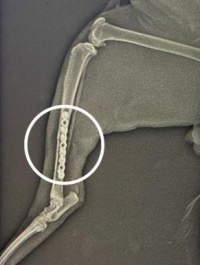

TİBİA KIRIĞINDA OSTEOSENTEZ – KEDİ